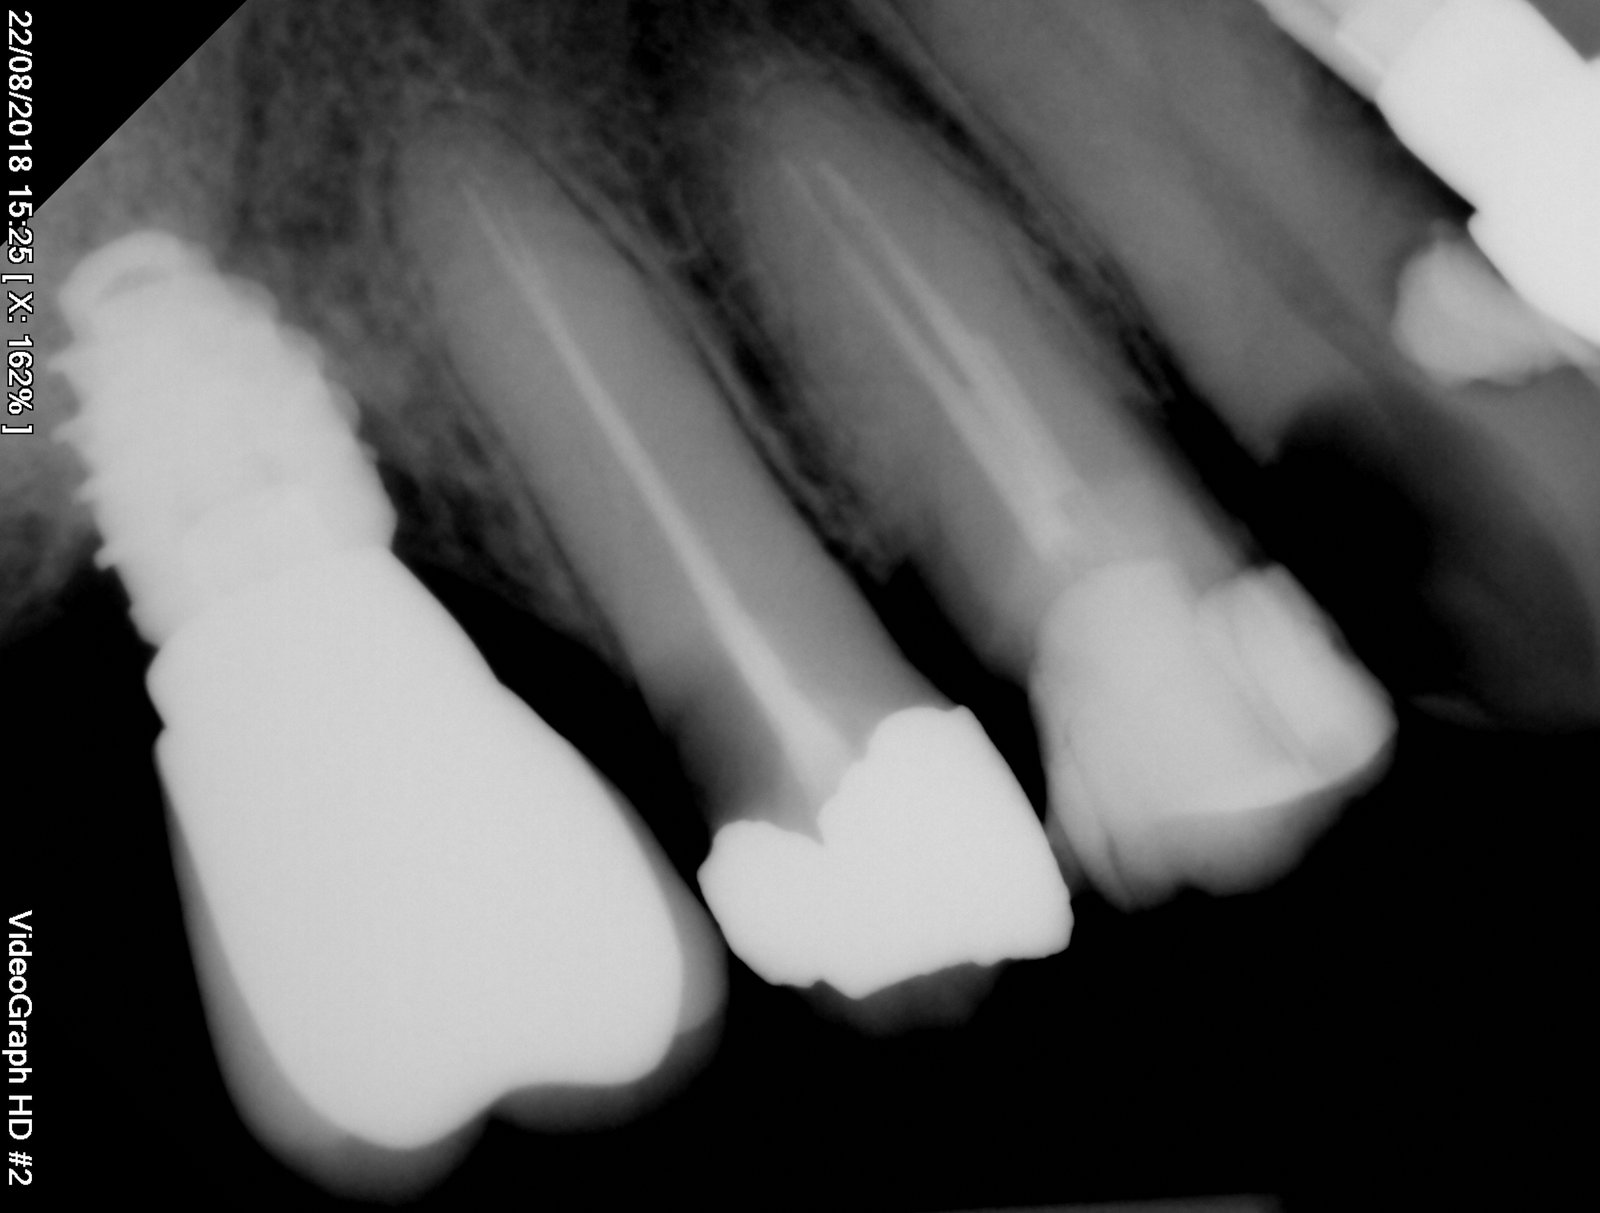

Estimados compañeros...necesito ayuda...cómo lo veis? Alguna idea? Según el paciente puestos en IDental y me trae esta Orto... Marca...compatibilidades... Gracias!